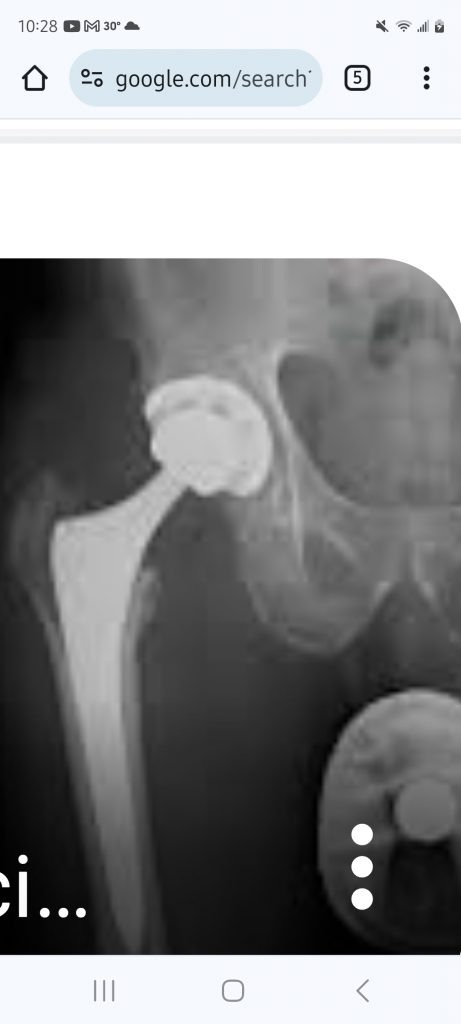

I was very pleased with my care team at HSS during my overnight stay after a total hip replacement. My surgeon, Dr. Elizabeth Gausden, did not disappoint. She performed an anterior hip replacement as we decided upon and she delivered. I was up and about in no time. Her team worked with me always returning my calls and answering my questions. I highly recommend HSS, Dr. Gausden and her team.

Hip Replacement